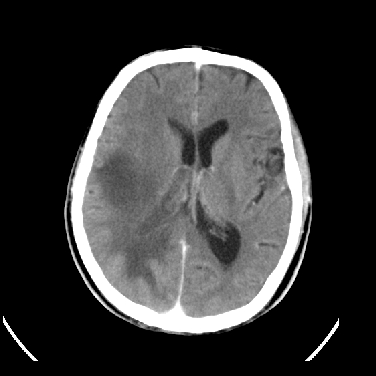

男,45岁,左侧肢体乏力1周。ex:胸片示:两肺团块状、斑片状密度增高影,其内可见小空洞。支纤镜、经皮肺穿示:干酪样物。

结合病史考虑结核性脑炎脑膜炎,伴脑脓肿形成

考虑右侧顶叶脑脓肿形成。

同意“考虑结核性脑炎脑膜炎,伴脑脓肿形成”的意见,不轻易怀疑肿瘤。

考虑结核性脑炎脑膜炎,伴脑脓肿形成。

考虑右侧顶叶脑脓肿(结核性?)。

结核性脑脓肿可能大

结合病史考虑结核性脑炎脑膜炎,伴脑脓肿形成,囊变转移瘤不除外